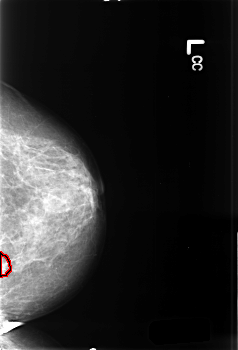

B_3374_1.LEFT_CC

LEFT_CC LINES 4544 PIXELS_PER_LINE 3088 BITS_PER_PIXEL 12 RESOLUTION 50 OVERLAY

FILE: B_3374_1.LEFT_CC.OVERLAY

TOTAL_ABNORMALITIES 1

ABNORMALITY 1

LESION_TYPE CALCIFICATION TYPE PLEOMORPHIC DISTRIBUTION CLUSTERED

LESION_TYPE MASS SHAPE IRREGULAR MARGINS ILL_DEFINED

ASSESSMENT 4

SUBTLETY 3

PATHOLOGY MALIGNANT

TOTAL_OUTLINES 1

BOUNDARY